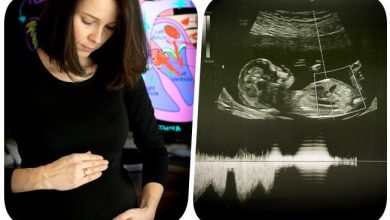

Uratujmy serduszko Tymka!

„Wiemy, że po przyjściu na świat nasz synek doświadczy bardzo trudnego czasu. Czasu wypełnionego bólem, strachem, brakiem bezpieczeństwa, które w…